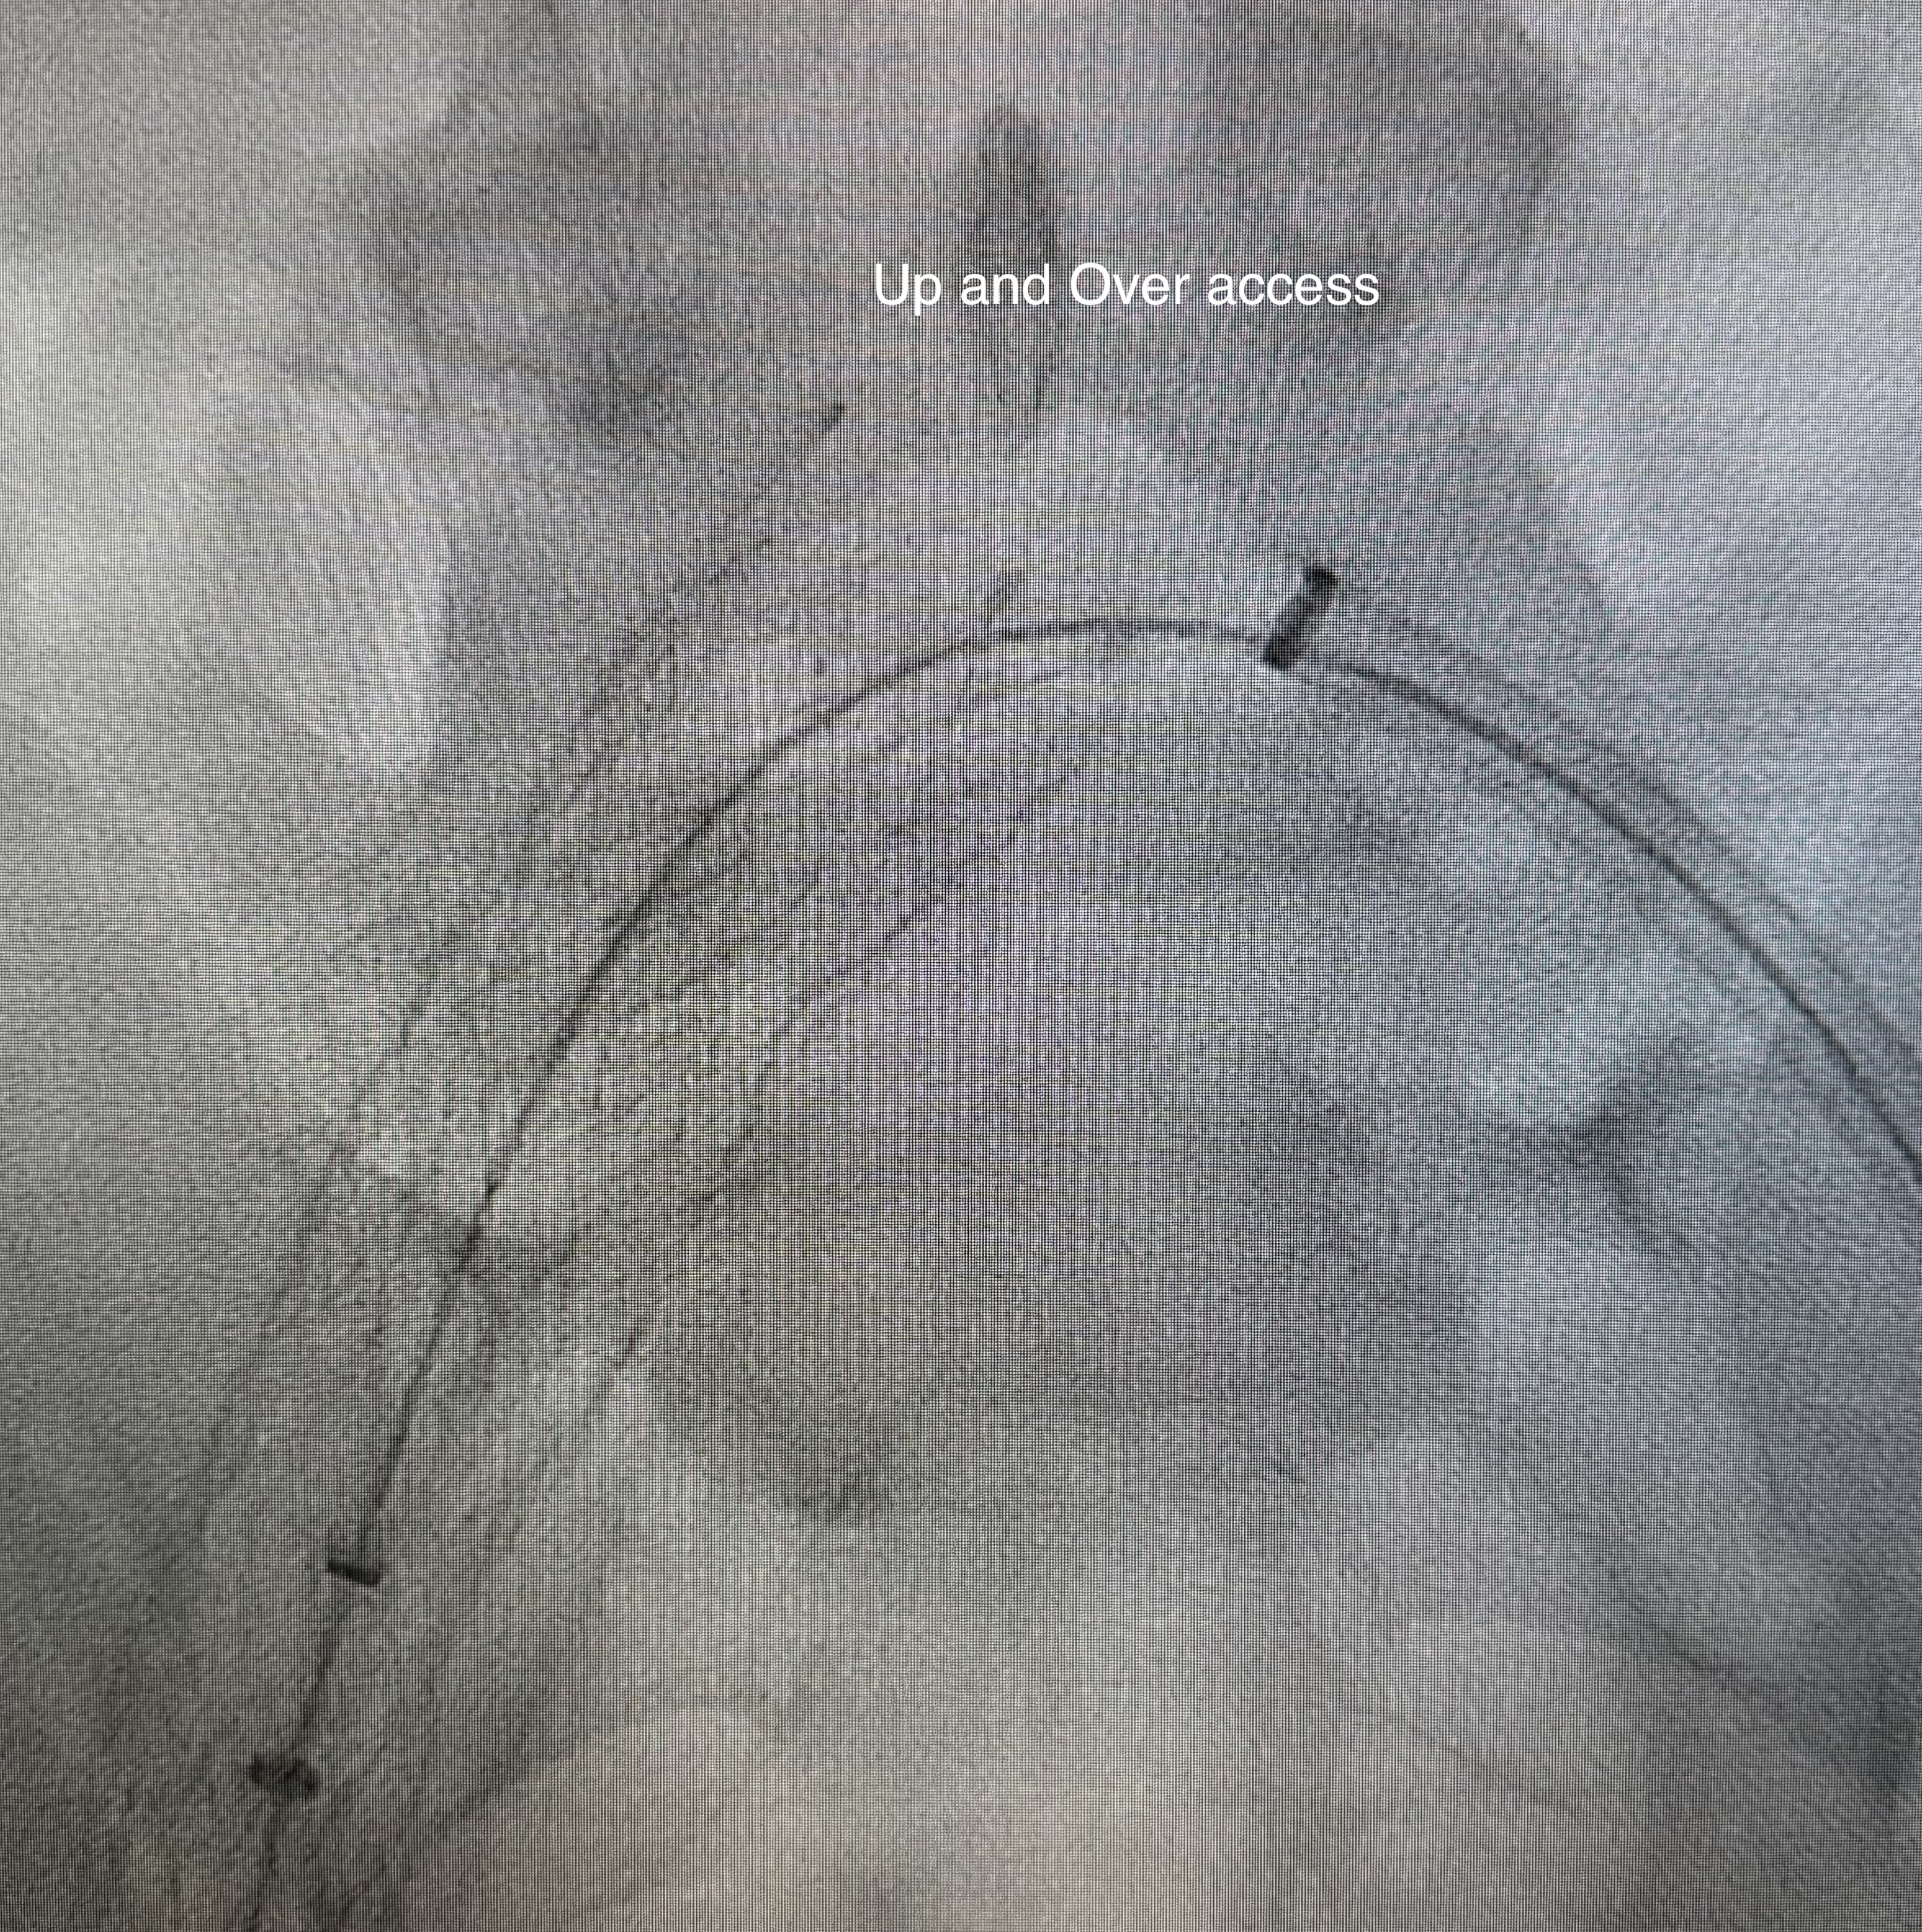

Accesses at right and left popliteal veins were established. A FlowTriever disc was inserted as a temporary inferior vena cava filter via the right popliteal access. Wire was passed through the thrombosed left common iliac to femoral stent. Aspiration thrombectomy was performed and aspirated small amount of chronic blood clots. Subsequent, an "up and over" access was established with a 16 French aspiration catheter inserted through the right popliteal access to the left common iliac stent. The Clottriever catheter was inserted through the left popliteal access into the aspiration catheter. The Clottriever catheter was then retrieved, with simultaneous forward movement of the aspiration catheter to protect the collection basket of the Clottriever catheter from damaging the left common iliac stent during the retrieval process. Moderate amount of blood clots were retrieved with multiple attempts. Balloon angioplasty was then performed and blood flow through the common iliac vein was restored. There was significant improvement in terms of lower limb swelling after the procedure and the patient was discharged later with anticoagulation therapy.